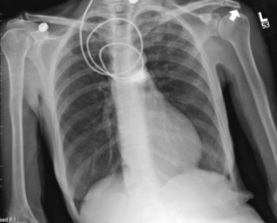

Identify the following anatomical structures